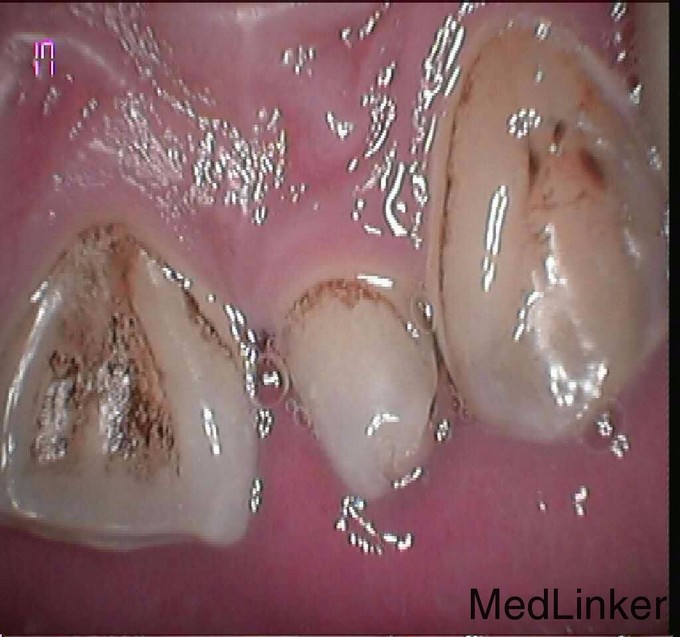

患者男上前牙过小,烤瓷冠修复

上前牙烤瓷修复术后